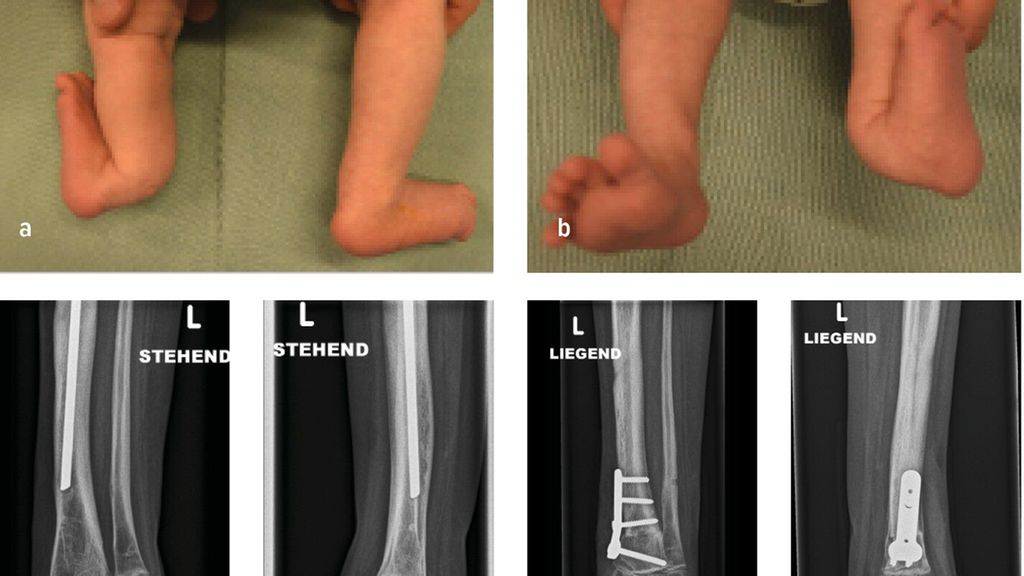

Die genaue Epidemiologie und Pathogenese des posteromedialen Bowings, auch bekannt als Crus valgum recurvatum, sind unbekannt. Einzelne dokumentierte Fälle in der Literatur lassen jedoch darauf schließen, dass es sich hierbei um eine sehr seltene Fehlstellung des Unterschenkels handelt, die vor allem die linke Extremität betrifft.15,16 Die Biegung der Tibia nach hinten und zur Körpermitte beträgt zwischen 25 und 70° und tritt typischerweise am Übergang vom mittleren zum distalen Drittel auf. In ausgeprägten Fällen kann die Fehlstellung bis zu 90° betragen. Der Fuß des Neugeborenen kann in schweren Fällen auf der Schienbeinkante zu liegen kommen. Bildlich repräsentiert dies der Fall eines 6 Wochen alten Mädchens mit posteromedialem Bowing der linken unteren Extremität mit typischer Biegung am Übergang vom mittleren zum distalen Drittel. Hier kommt der Fußrücken an der Unterschenkelkante zu liegen (Abb.3a,b). Differenzialdiagnostisch ist dabei an eine Calcaneo-valgus-Fehlstellung des Fußes zu denken.16 Eine spontane Rückbildung der Fehlstellung wird im Laufe des Wachstums bis zum 4.–5. Lebensjahr beobachtet.15 Konservative Maßnahmen beschränken sich initial auf sanfte Fußmassagen des Neugeborenen. In schweren Fällen kann eine graduelle Gipsredression eingesetzt werden.14

Abb. 3: 6 Wochen altes Mädchen mit posteromedialem Bowing der linken unteren Extremität (a+b) sowie postoperative Bildgebung

Verbleibende Fehlstellungen, insbesondere Rekurvation der Tibia, Beinlängendifferenz, Torsionsfehler oder Valgusfehlstellung der Tibia oder des Sprunggelenkes, bedürfen einer chirurgischen Intervention. Die dysplastische keilförmige Wachstumsfuge an der distalen Tibia begünstigt in einigen Fällen die Valgusfehlstellung im Sprunggelenk. Im Rahmen der Bildgebung präsentiert sich in dieser Abbildung ein 6 Jahre altes Mädchen mit einer selten auftretenden verbleibenden Valgusfehlstellung im Sprunggelenk bedingt durch eine dysplastische keilförmige Wachstumsfuge bei Z.n. Korrektur und Verlängerung mittels Fixateur externe und Stabilisierung mit intramedullärem Nagel (Abb.3c,d). Als chirurgische Therapien stehen hierfür die Wachstumslenkung an der distalen Tibia oder akute (supramalleoläre Korrekturosteotomien (Abb.3e,f) bzw. graduelle (externer Fixateur) Korrekturen zur Verfügung. Verbleibende Beinlängendifferenzen können durch eine Wachstumsbremsung der kontralateralen Seite bei geringer Beinlängendifferenz oder mittels gradueller Distraktionsosteogenese (externer Fixateur) therapiert werden.14,16,17